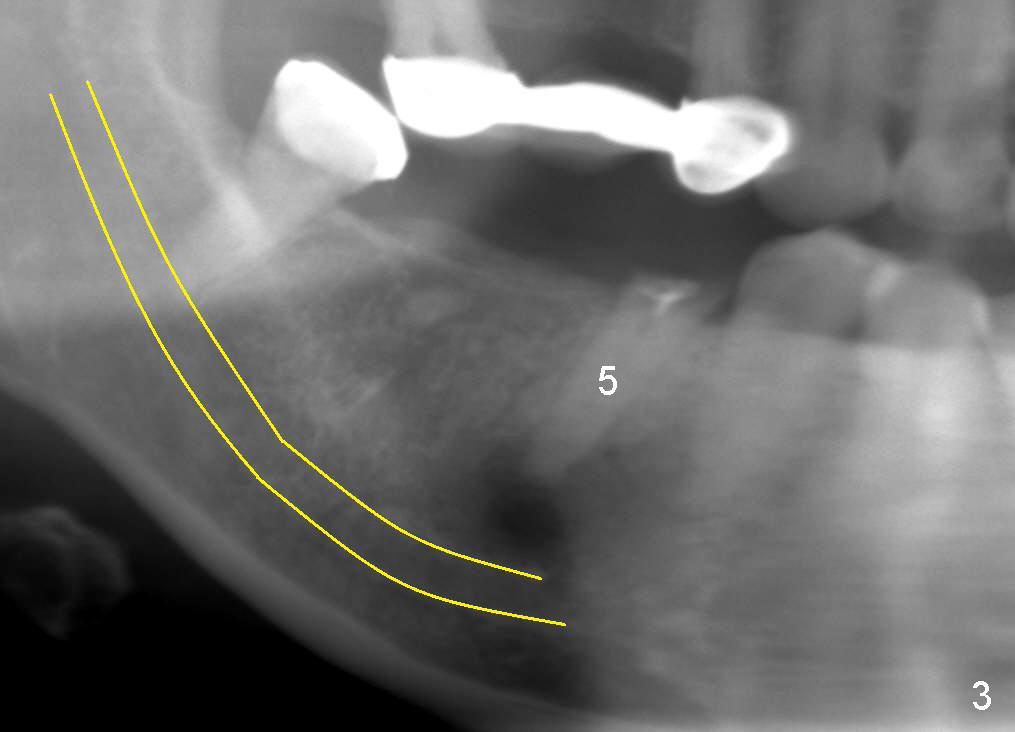

A 49-year-old lady cannot chew with the lower right bridge (Fig.1: from the 2nd premolar (5) to the third molar (8)). Insertion of gutta percha (Fig.2 >) points to the apical radiolucency of the anterior abutment (*). The bridge is sectioned between the pontic of 2nd molar and the retainer of the posterior abutment. The anterior segment of the bridge falls out. The anterior abutment is non-salvageable due to severe 2nd caries (Fig.3 (5) part of panaramic X-ray). The yellow lines denote the inferior alveolar nerve. In brief, the apex of the affected tooth is most likely closely associated with the mental loop.

If the immediate implant (5x20 mm) is placed within the confinement of the socket, the integrity of the nerve will be not violated (Fig.4). The patient returns for the surgery 2 months after bridge removal. The root stump is cleaned so well that the buccal apical fistula disappears (Fig.5). The mesiodistal dimension of the root is 5 mm, whereas buccolingual 6.5 mm. Infiltration (not block) anesthesia is administered. The root is extracted. A 2 mm pilot drill drops by itself into the socket (Fig.6 D); the loop should overlap the apex of the socket.